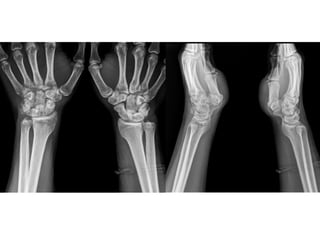

This presentation discusses various topics related to the wrist including static scapholunate ligament dissociation, dorsal ganglion cysts originating from the dorsal capsulolunate septum, treatment of scaphoid pseudarthrosis using a bone graft from the distal radius placed under the extensor tendons, and proximal pole scaphoid pseudarthrosis treated with capitolunate arthrodesis. It also thanks attendees and provides instructions for accessing the presentation online.